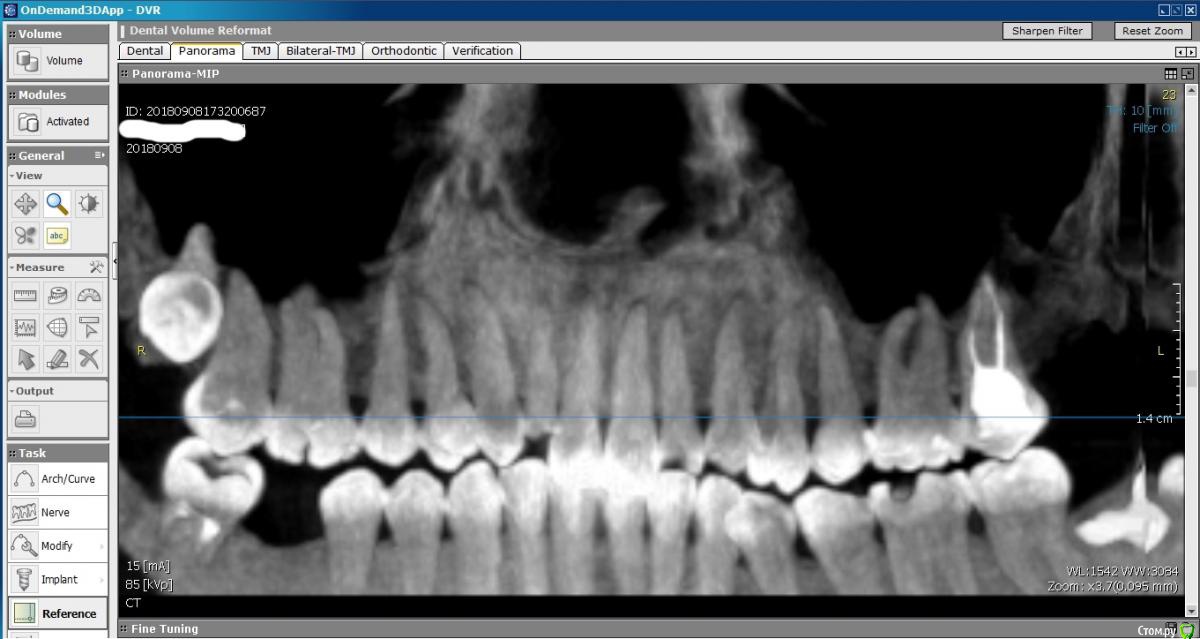

DmitrySH Опубликовано 13 декабря, 2018 Поделиться Опубликовано 13 декабря, 2018 1. На КТ надо нормально посмотреть зуб 27. По этим снимкам мне он не очень нравится2. Убрать 38 Ссылка на комментарий

Tesh Опубликовано 30 января, 2019 Автор Поделиться Опубликовано 30 января, 2019 Ссылка на КТ:https://drive.google.com/file/d/1bjdRAtYwsW0Rh3z1XAJuYumeF1-fvTwe/view?usp=sharing Ссылка на комментарий